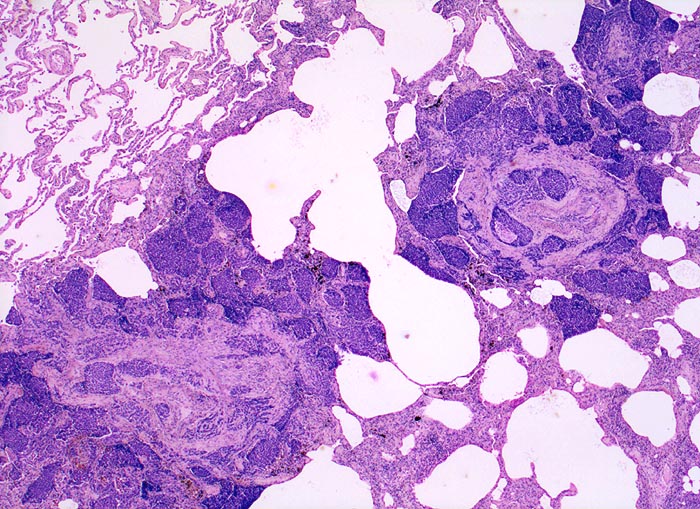

• Sternförmiges Karzinom mit zentraler Vernarbung mit reichlich schwarzem Anthrakosepigment.

• In den sternförmigen Ausläufern finden sich erweiterte Endothelausgekleidete Lymphgefässe in der Nachbarschaft von Blutgefässen.

• Die erweiterten Lymphgefässe enthalten solide Tumorzellaggregate.

• Peritumorales Lungenemphysem (Traktionsemphysem).